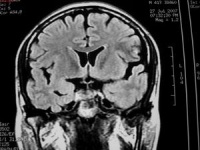

MRI表现[编辑 | 编辑源代码]

在脑部动静脉畸形的诊断上有较大优越性,尤其是后颅窝病灶,诊断价值大于CT。因此,当怀疑病人患有脑血管畸形时,MRI为首选的影像检查手段。①脑动静脉畸形的血管成分,表现为成团状、网状分布的无信号流空血管影。其中供血动脉,在T1和T2加权像上因流空现象而表现为低信号或无信号影。引流静脉则因血流缓馒,T1加权像呈低信号,T2加权像为高信号像。血管的钙化表现为低信号或无信号暗区。动静脉畸形中的血栓,在T1和T2加权像均表现为低信号夹杂等信号或高信号和低信号内夹杂高信号影。②动静脉畸形出血形成血肿,则表现为T1和T2加权像变化和其他原因所致血肿相似。亚急性期血肿,在T1和T2加权像上均为高信号,随时间延长,血肿在T1加权像上信号逐渐变为等信号或低信号,T2加权像上仍为高信号。

4、头部MRI:优于CT,不仅能显示畸形血管及其周围脑组织,还可区别出血与钙化。MRI血管造影相可提高畸形血管团的诊断率。

3、头部磁共振:优于CT,不仅能显示畸形血管及其与周围脑组织的关系,还可区别出血与钙化。